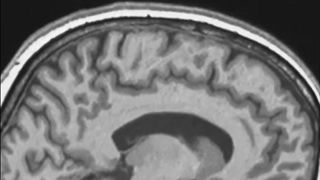

'Backward and upward and tilted': Spaceflight causes astronauts' brains to shift inside their skulls

By Josh Dinner published

Space apparently changes your frame of mind in more ways than one.